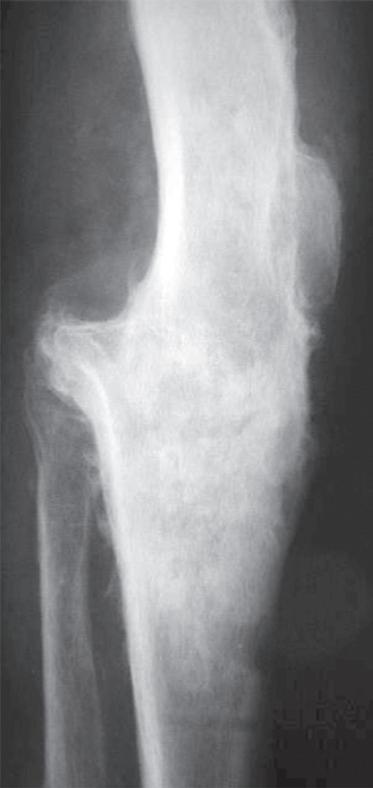

Obr. 19.3: Valgózní deformita kolenního kloubu (a) a rentgenový  nález úhlové deformity s nálezem pokročilých artrotických  změn (b)

(předozadní a bočná). Na rentgenovém snímku se gonartróza zpočátku projevuje přihrocením interkondylické eminence a subchondrální sklerózou v místě přetížení, později zúžením, případně až zánikem kloubní štěrbiny, vznikem osteofytů, pseudocyst a případnou úhlovou deformitou. Dle nálezu rovněž klasifikujeme stupeň gonartrózy podle Kellgrena-Lawrence (viz kap. 17, obr. 19.4), což má praktický význam v indikaci farmakoterapie i balneoterapie.